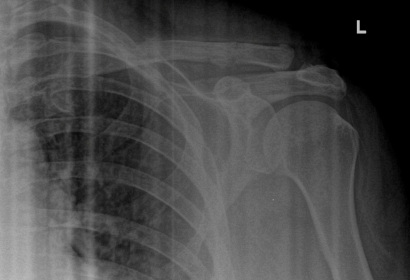

Displaced Clavicle Fracture with Butterfly Fragment